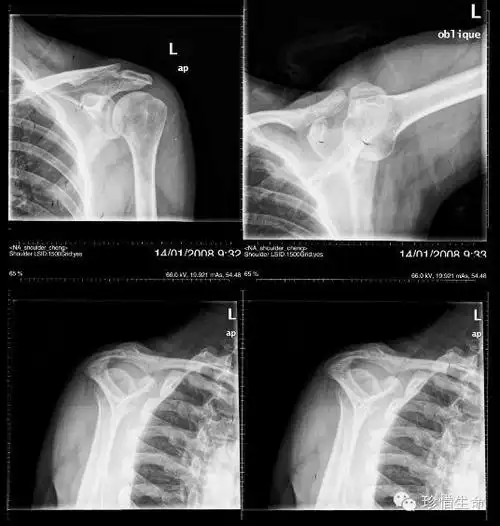

肩关节x线检查体位大全